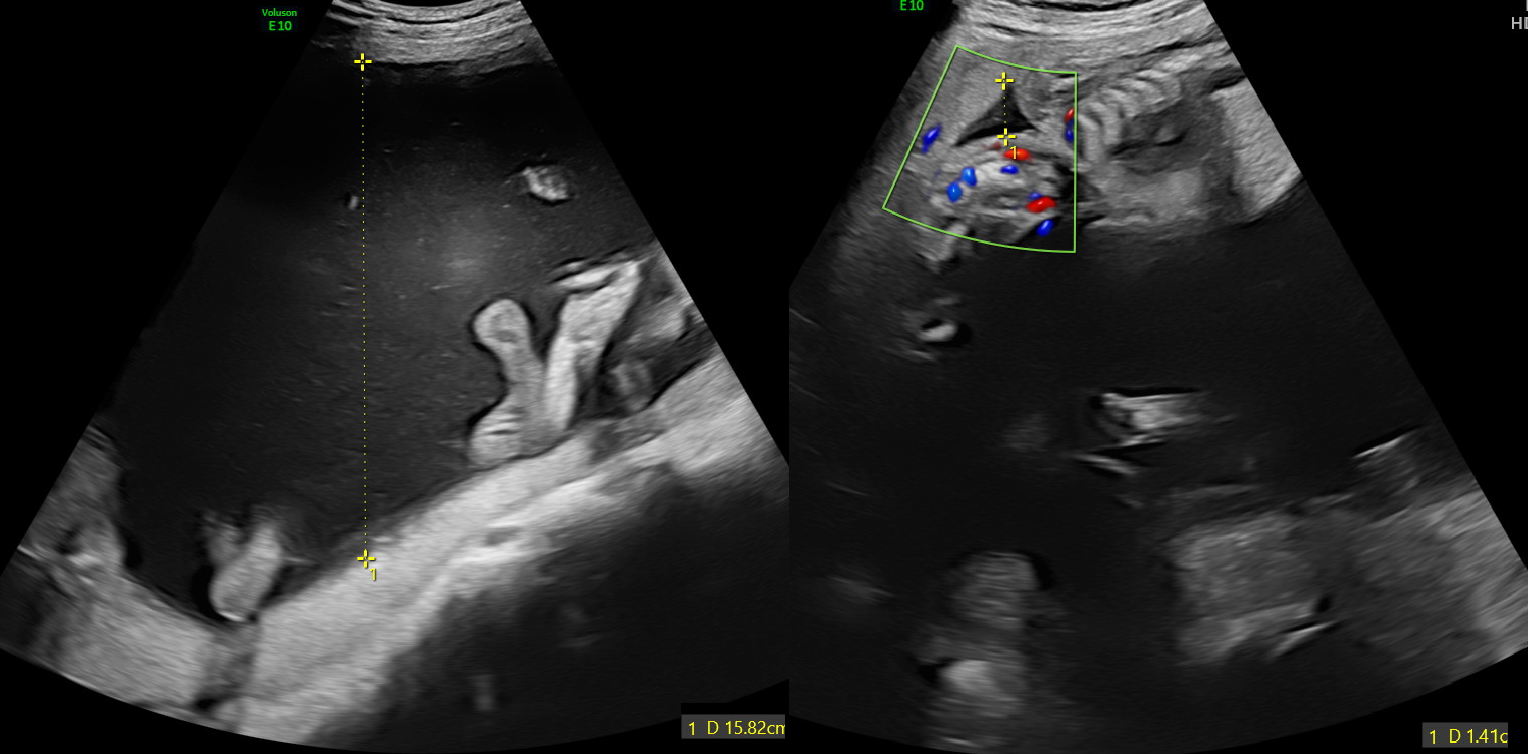

我們通常會量測SDP(single deepest pocket,也就是垂直最深的深度)。一般來說,一個羊水量<2cm,另一個羊水量>8cm,就已經是第一級的TTTS。

圖左的胎兒羊水量過多,圖右的胎兒羊水只剩一公分。#羊水過多會造成孕婦的肚子變大,容易引起早期的宮縮,進而造成早產的風險增加。